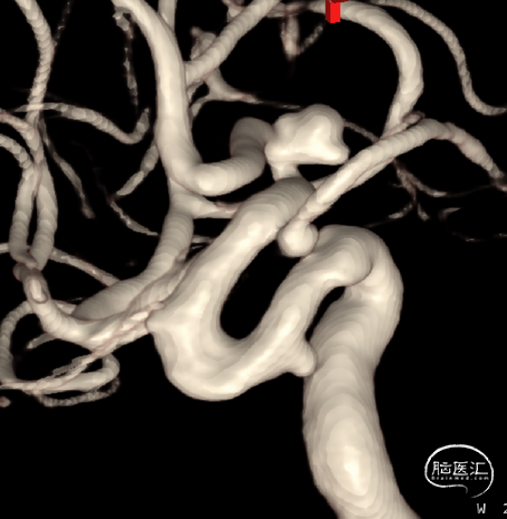

一位64岁男性,因间断胸痛3年入院心内科,入院后头颅CTA发现前交通动脉瘤,转我科继续治疗。既往有高血压,高血脂病史。体检无神经系统异常。

患者术前DSA

通过DSA检查在前交通处发现动脉瘤,立即用UKnow®动脉瘤稳定性评估,评估显示,该动脉瘤属于高风险,建议患者手术。通过风险评分,与患者沟通,患者表示同意手术,于是我们对其进行了动脉瘤栓塞术,愈后良好!